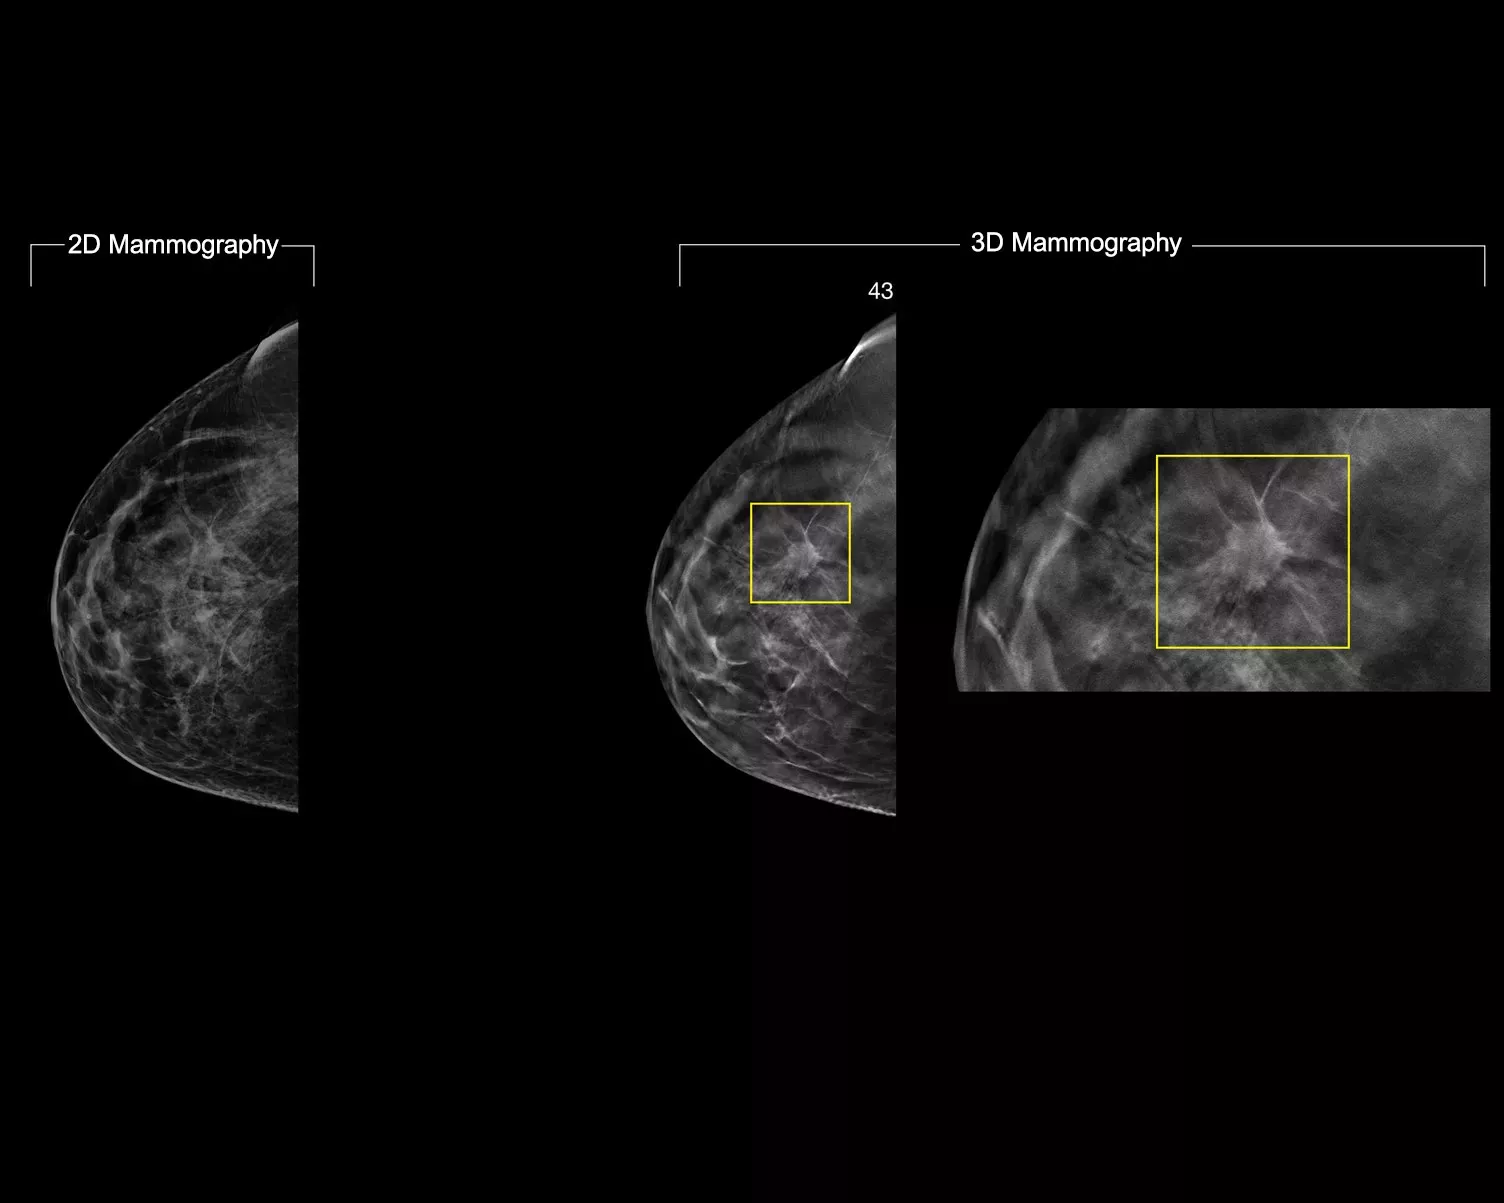

Un algorithme d’intelligence artificielle conçu pour aider les radiologues à effectuer des diagnostics et à détecter un cancer du sein1-3 à partir d’images de tomosynthèse obtenues à l’aide du système Hologic Dimensions Mammography®. L’algorithme localise les lésions susceptibles de représenter un cancer du sein en étudiant chaque coupe de l’ensemble des images de tomosynthèse. Les zones suspectes sont mises en évidence sur le poste de travail du radiologue pour permettre une lecture simultanée et aider à l’interprétation.

L’algorithme recherche les 3 principaux groupes de lésions suspectes : calcifications, masses, densités et distorsions ; ainsi que les combinaisons de ces lésions. Les données de sortie peuvent varier selon les postes de travail.